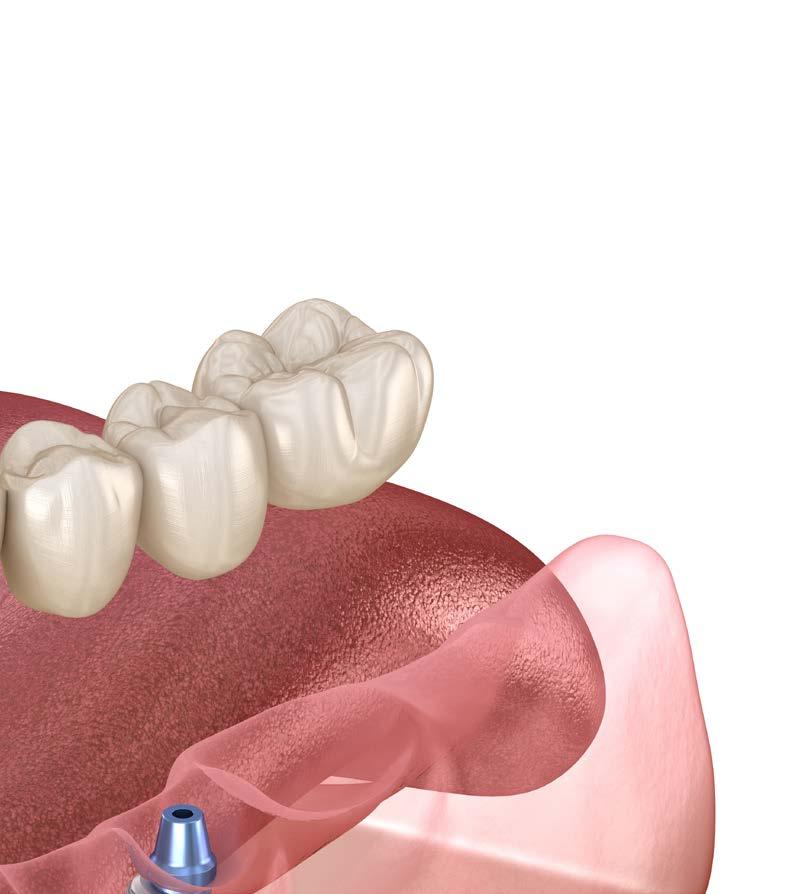

Todos los dientes conservados reciben un mantenimiento periodontal riguroso (Figura 4-6). Transcurridos 2 meses, comenzamos con la rehabilitación del maxilar superior mediante implantes. Durante este tiempo se lleva a cabo la inserción y rehabilitación provisional mediante prótesis de carga inmediata de la mandíbula. Para elaborar la planificación de los implantes a colocar se realiza en primera instancia un TAC, observándose en el mismo que existe un déficit de altura en todo el maxilar superior, siendo más acusada la atrofia en altura en la zona de los molares. En el primer cuadrante, tenemos una altura ósea de 5.5 mm por lo que podemos planificar la colocación de un implante extracorto (5.5 mm de longitud y 5.5 mm de diámetro) con elevación de seno transcrestal (Figura 7). En el segundo cuadrante, existe una atrofia ósea en altura mucho mayor con menos de 1 mm de altura, existiendo áreas donde se produce una ruptura

Transcurridos 6 meses desde la elevación de seno convencional, ya podemos llevar a cabo la colocación de los implantes, una vez madurado el injerto óseo. En el cone-beam de control realizado en este momento,

observamos cómo tenemos altura ósea suficiente para su inserción y optamos por la colocación de un implante de 7.5 mm de longitud y 5.5 mm de diámetro (Figura 9). El uso de este diámetro nos asegura una estabilización tridimensional óptima en el lecho receptor, minimizando la aparición de micromovimientos durante la fase de integración. En cuanto a la longitud del implante, aunque sería viable utilizar uno más

largo, no lo consideramos necesario. Con una longitud de 7.5 mm es suficiente para garantizar un comportamiento biomecánico estable a largo plazo, además de que esta opción nos permite ser más conservadores con el lecho óseo neoformado receptor. En esta misma fase quirúrgica se realiza la segunda cirugía de los implantes del primer cuadrante colocados mediante la elevación transcrestal en

la fase quirúrgica previa y se cofecciona una prótesis de carga progresiva, aún sin englobar el implante colocado en la elevación de seno del segundo cuadrante. La prótesis se confecciona sobre transepiteliales, atornillada y se elabora con barras preformadas, por lo que puede generarse pocas horas después de la segunda fase y la toma de medidas. En este momento se decide la exodoncia de los caninos

La prótesis de carga progresiva superior, se mantiene durante 5 meses. Posteriormente, con el patrón oclusal estable se procede a la carga del último implante del segundo cuadrante (el insertado en la elevación de seno convencional) y se realiza la prótesis definitiva. Para la realización de esta prótesis, se confecciona un encerado que puede ser probado en boca y una vez ajustado puede ser escaneado para la confección digital de la prótesis. La estructura se diseña y se

Las prótesis tanto para los implantes colocados en el primer cuadrante (elevación transcrestal) como para el segundo cuadrante (elevación convencional), son confeccionads con una estructura metálica fresad por CAD-CAM con la adición final de la cerámica de forma tradicional y se dividen en 3 sectores (posterior derecho, central y posterior izquierdo). Finalmente, solo pueden ser conservados los molares inferiores, pero son suficientes para que aporten al paciente una propiocepción